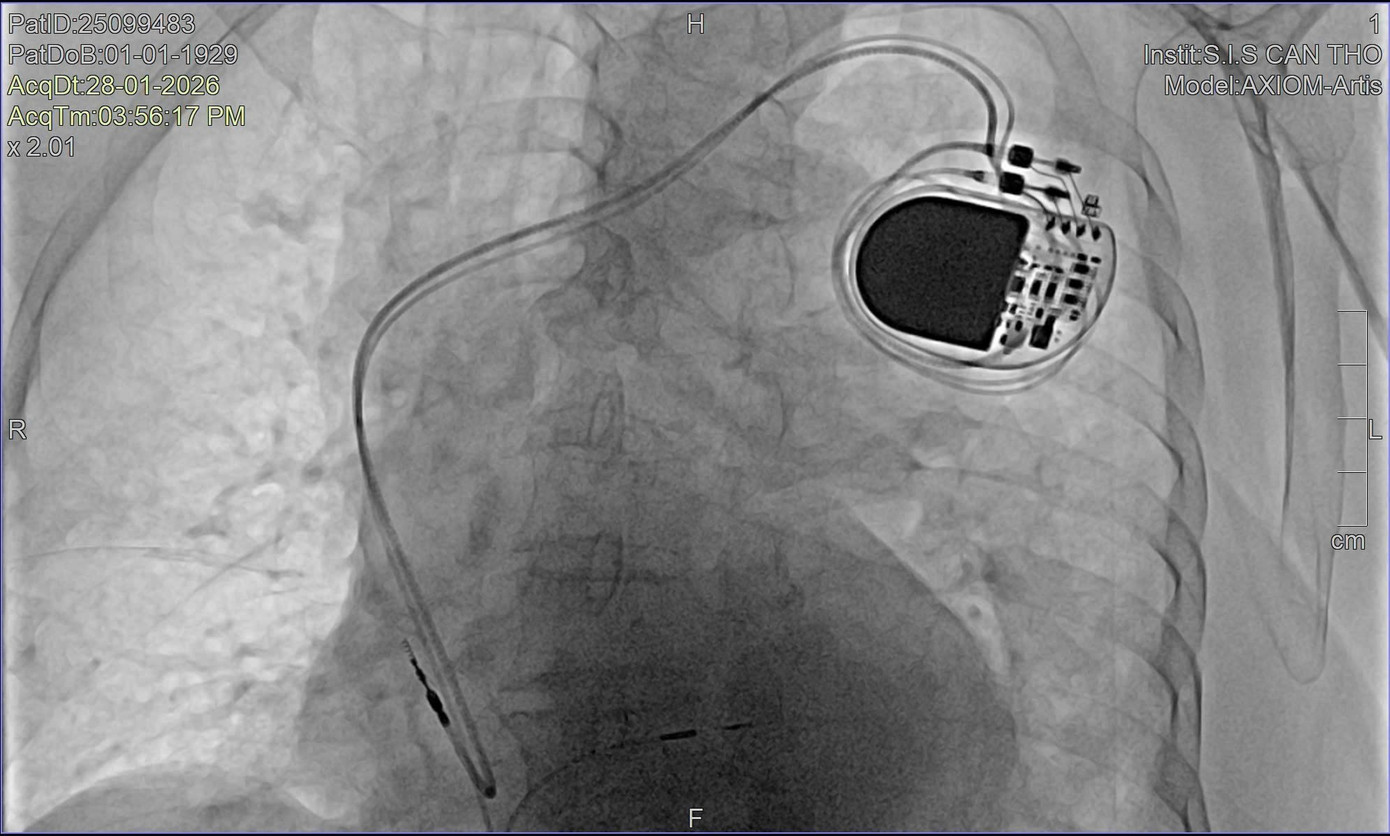

Phương pháp cấy máy tạo nhịp bó nhánh trái lần đầu tiên tại Việt Nam được thực hiện thành công trên bệnh nhân 97 tuổi

Theo BS-CKII Nguyễn Mạnh Cường, Phó khoa Nội Tổng hợp, do bệnh nhân tuổi rất cao và rối loạn nhịp nghiêm trọng, ê kíp điều trị đã nhanh chóng đặt máy tạo nhịp tạm thời để ổn định huyết động. Song song đó, bệnh nhân được làm xét nghiệm máu, chụp X-quang phổi và chụp mạch vành bằng DSA để đánh giá toàn diện tình trạng tim mạch.

Kết quả chụp mạch vành cho thấy cụ bị hẹp mạch vành mức độ vừa, phù hợp với tuổi, được điều trị nội khoa. Sau khi tình trạng toàn thân ổn định, hội đồng chuyên môn thống nhất chỉ định cấy máy tạo nhịp vĩnh viễn bằng kỹ thuật bó nhánh trái – một phương pháp tiên tiến đang được triển khai tại bệnh viện trong những năm gần đây.

Theo các bác sĩ, đây là trường hợp bệnh nhân lớn tuổi nhất tại Việt Nam được thực hiện kỹ thuật cấy máy tạo nhịp bó nhánh trái. Khác với phương pháp cấy máy tạo nhịp truyền thống, kỹ thuật bó nhánh trái giúp xung điện được dẫn truyền gần với sinh lý tự nhiên của tim, duy trì sự co bóp đồng bộ của thất trái, từ đó giảm nguy cơ suy tim lâu dài. Đối với người cao tuổi, phương pháp này mang lại lợi ích kép, vừa đảm bảo hiệu quả điều trị rối loạn nhịp, vừa hạn chế biến chứng.